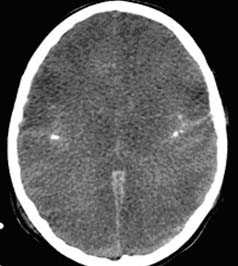

2. Диффузное аксональное повреждение. Диффузное аксональное повреждение (ДАП, синоним — диффузное повреждение белового вещества по механизму сдвига) возникает в результате приложения тяжелой деформирующей силы сдвига во время высокоскоростной травмы. Пациенты находятся в глубокой коме со стволовыми симптомами. Большинство повреждений происходит по средней линии с формированием небольших повреждений в глубоких слоях белого вещества больших полушарий, мозолистом теле и стволе головного мозга. В некоторых случаях выявляется небольшой осадок крови в одном из боковых желудочков, что вызвано разрывом его эпендимы. Полный объем повреждения можно оценить только на МРТ.

3. Подкорковые повреждения серого вещества. Подкорковые повреждения серого вещества иногда (3-5%) находятся в базальных ганглиях и таламусе.

Они, как правило, связаны с неблагоприятным прогнозом. Постулируется механизм повреждения мелких артерий силой сдвига.

е) Диффузное аксональное повреждение (ДАП). ДАП представляет собой патологическое повреждение аксонов в результате травмы по механизму ускорения/замедления или вращения. Типичные локализации ДАП находятся на границе серого и белого вещества, в мозолистом теле, дорсолатеральном отделе ствола мозга, своде, базальных ядрах и внутренней капсуле.

Ключевые данные визуализации:

- При легком ДАП данные КТ часто нормальные.

- При КТ может быть выявлен умеренный отек мозга или микрокровоизлияния (20-50%) в местах повреждения или очаговое поражение (10%).